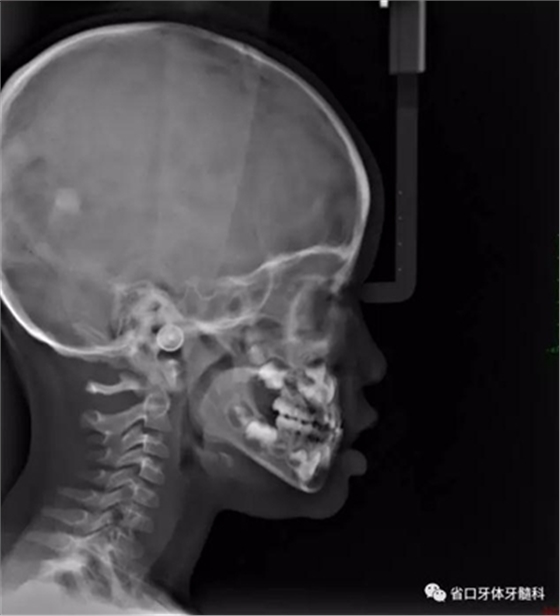

圖10 側(cè)位片